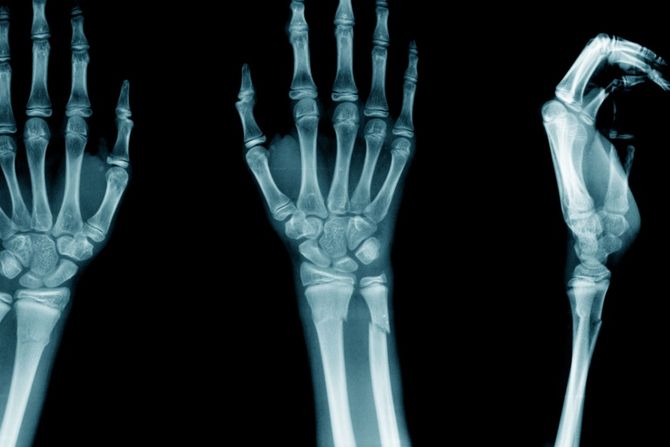

Prelom ručnog zgloba (fraktura zgloba) je najčešća trauma tokom zimskog perioda kada su ulice prekrivene snegom i ledom. Fraktura zgloba ruke može da utiče na bilo koju od 10 kostiju koje čine podlakticu i zglob, a najčešće je pogođena radijusna kost. Padovi na ispruženu ruku su najčešći uzrok preloma zgloba zbog čega uvek treba potražiti  medicinsku pomoć kako bi se dobila odgovarajuća dijagnoza i lečenje.

Prelom ručnog zgloba podrazumeva lomljenje bilo koje od 10 kostiju

Prelom ručnog zgloba može da se javi na bilo kojoj od 10 kostiju koje čine podlakticu i zglob. Te kosti su:

- Radijus: Veća kost podlaktice- Ulna: Manja kost podlaktice- Karpalne kosti: Osam malih kostiju koje se nalaze u osnovi šake.

Najčešći prelom kosti zgloba je radijus, a hirurzi šake ovo nazivaju prelomom distalnog radijusa.